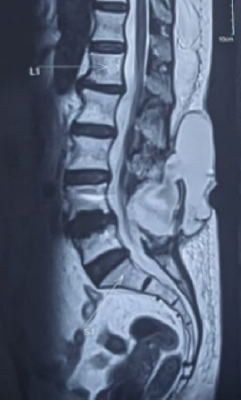

Dorsal Claviculectomy For Treatment Of Brachial Plexus Injury After Scapulothoracic Fusion: A Case Report And Literature Review

Huda S Saadeh , Yovag Morag , Ann Little , Yamaan S Saadeh

………………………………p.14-20